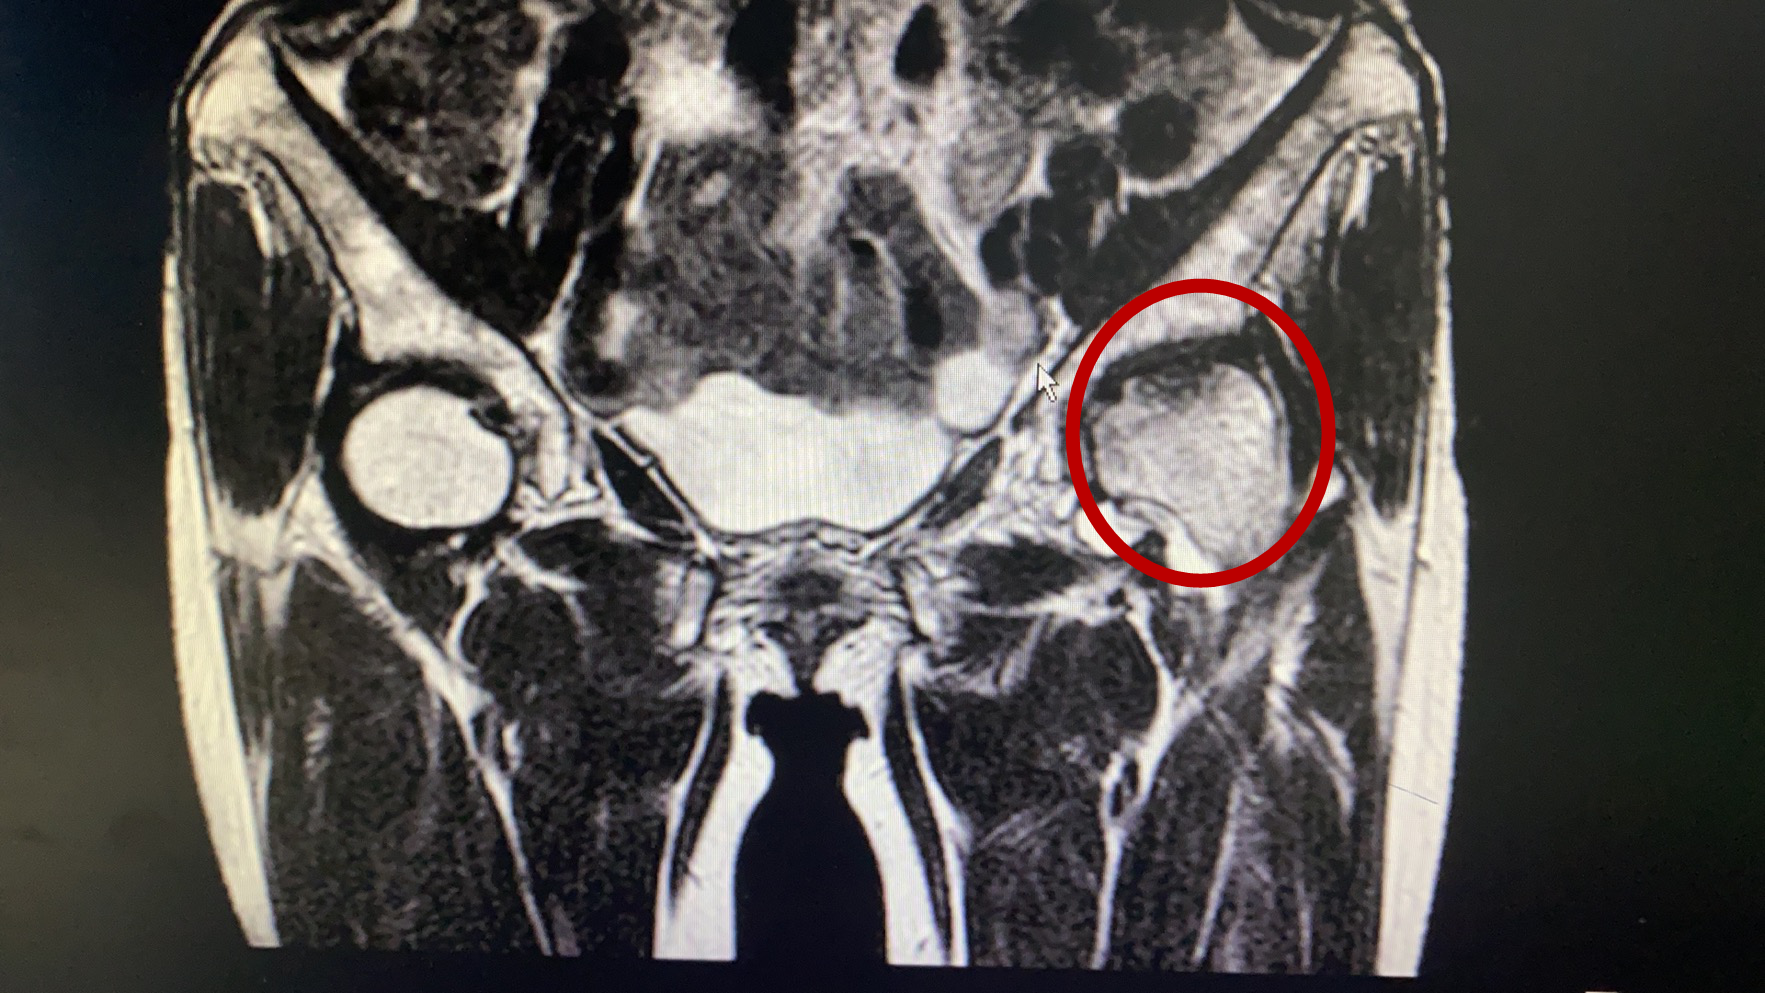

术后影像

骨关节专家林石明副院长及其医疗小组成员,经过反复研究患者的核磁共振及CT三维血管重建等资料后,考虑为左侧股骨头坏死,程度在二期到三期之间,具有“带血管蒂腓骨骨移植”手术指征。目前国际上公认“带血管蒂骨移植”这项保髋技术成功率较高,但该手术技术难度较大,需要把小腿上约8cm腓骨连同临近的腓骨动脉血管截一段下来,植入股骨头颈的坏死区域,在显微镜下,将腓骨动脉与股骨头临近血管进行对接缝合,重建血供让坏死股骨头获得新生。该手术一旦成功,将为林女士保留住髋关节功能,能较快恢复日常劳动,且费用较低。